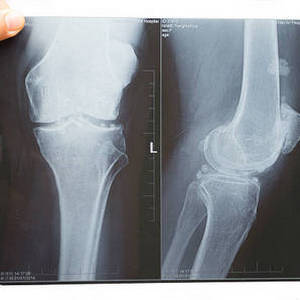

На фото коленного сустава видно, что связок гораздо больше. Только у надколенника есть собственная, которая крепится к бугристости большеберцовой кости, а также медиальная и латеральная поддерживающие. Малоберцовая кость также фиксирована задней и передней связками головки.

Коленный сустав испытывает колоссальные нагрузки, постепенно разрушаясь в течение жизни человека. Трудно встретить пациента после 45 лет с жалобами на колено и без диагноза «Артроз». Старение и износ хрящевой ткани диагностируют по рентгенограмме или МРТ, а также по симптомам – боли, скованности, отекам.